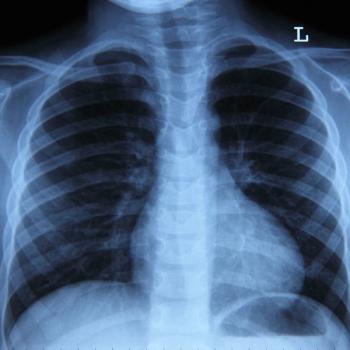

The first participant has been dosed on the phase 2 CONVERGE study evaluating NBTXR3 in stage III, unresectable non–small cell lung cancer.

Three phase 3 trials will assess datopotamab deruxtecan-based treatments in patients with nonsquamous non-small cell lung cancer.

This trial will assess an individualized neoantigen therapy plus Keytruda in some patients with non-small cell lung cancer.

Sequencing the novel drug, THIO, with Libtayo tended to be tolerable in patients with non-small cell lung cancer, recent research showed.

Researchers have initiated a phase 2 trial assessing a novel tyrosine kinase inhibitor that can potentially penetrate the central nervous system in patients with ALK-positive non-small cell lung cancer and other solid tumors.

The phase 2 ARROS-1 trial will investigate NVL-520 in patients with pretreated ROS1-positive non-small cell lung cancer or other solid tumors.